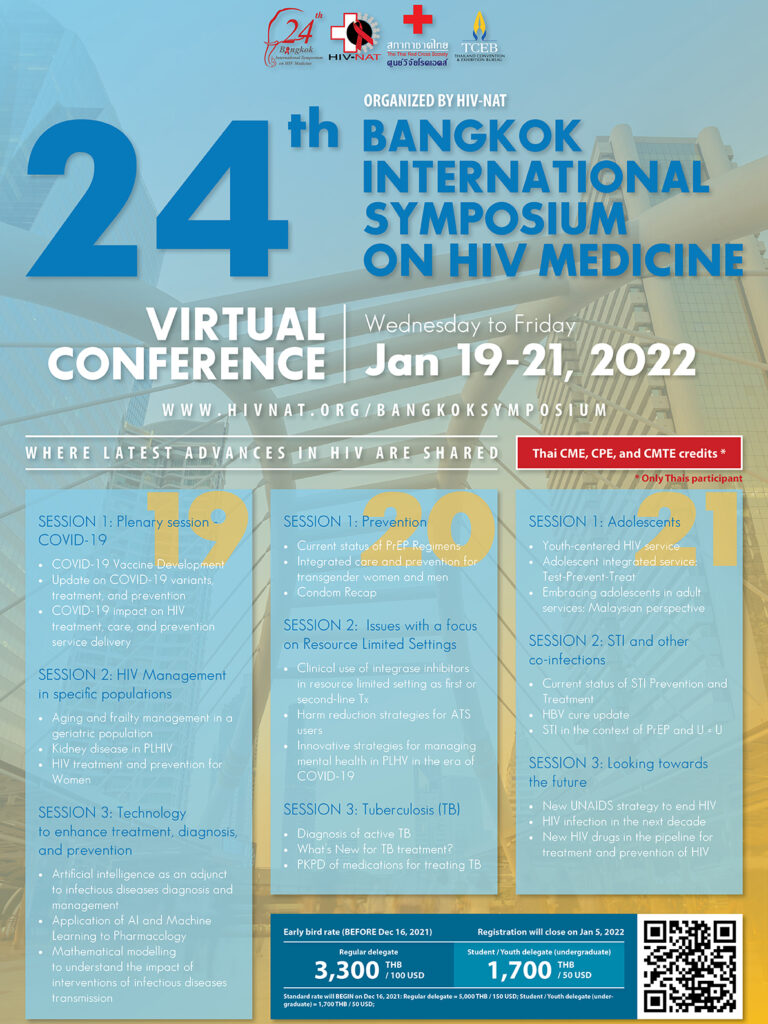

A long journey working with HIV from 1979-2025 หัวข้อบรรยาย: A long journey working with HIV from 1979-2025 บรรยายโดย: นพ.มนูญ ลีเชวงวงศ์ งานประชุมการดูแลรักษาผู้ติดเชื้อเอชไอวี/เอดส์ ครั้งที่ 24 (HIV/AID Workshop 2025) 28-29 สิงหาคม 2568 ห้องแกรนด์บอลรูม เอ บี และซี ชั้น 1 โรงแรมแมนดารินกรุงเทพ สามย่าน